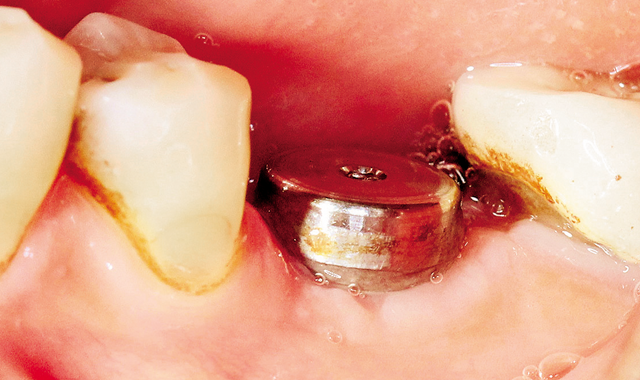

Fig. 4 4.2 mm final bur.

Drill sequence was completed with 4.2 mm Final bur (Fig. 4).